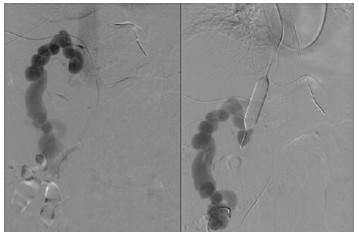

A 5F percutaneous transhepatic right portal access was obtained: the portography confirmed the presence of a high-flow mesocaval shunt with portal steal syndrome and subocclusion of the portal vein.

To avoid risk of nontarget embolization due to the high flow through the mesocaval shunt, a 9F jugular access was obtained to catheterize the origin of the mesocaval shunt on the caval side: a 14 × 40-mm balloon was inflated at shunt origin to stop the flow within the shunt, and an embolization with gelatin sponge and detachable coils and with N-butyl cyanoacrylate was performed under shunt exclusion (Figure 2).

After balloon deflation, complete embolization of the shunt with partial restoration of hepatopetal flow was observed, despite the finding of an increased flow through the coronary vein, which was subsequently occluded with embolization with detachable coils.

Figure 2. Catheterization and Embolization of Mesocaval Shunt With Balloon at Shunt Origin